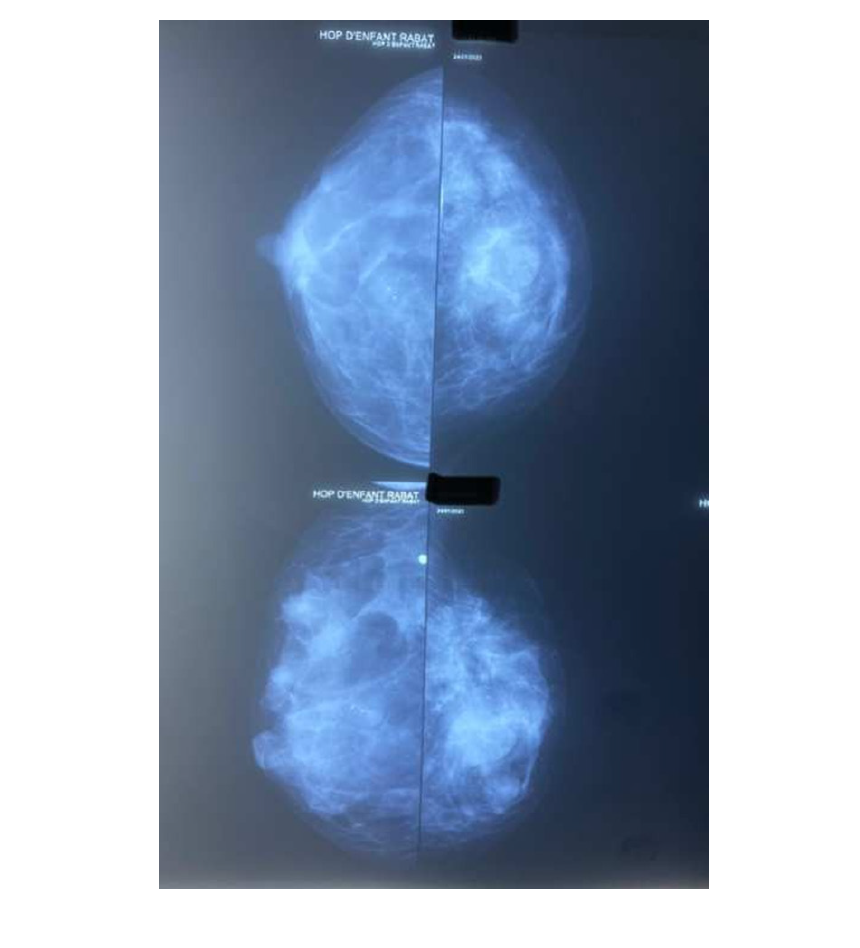

Upon her complaints, a sputum smear test was performed which came back positive and a whole Body-Scan was conducted. Thoracic Computed Tomography (CT) showed a calcified micronodule in the outer segment of the middle lobe, bilateral axillary nodes ranging from 0.5 to 9mm and a right mammary macrocalcification. Abdominal and pelvic CT revealed an abnormal hypodense lesion located on the right anteroinferior liver segment (V) with focal biliary tract enlargement associated with bilateral simple kidney cysts (Bosniak 1). Her pelvic CT showed an endometrial thickening of 17mm. Bone Window CT exhibited multiple peripheral and axial skeletal osteoblastic and osteolytic lesions particularly seated on the vertebral body of the 5th lumbar vertebrae disrupting the cortex. In order to further explore her mammary findings, a sonomammography was performed manifesting bilateral heterogenous hypoechogenic lesions with irregular borders associated to calcifications in the right mammary gland. Mammography on cranio-caudal and oblique projection showed an ill-circumcised lesion with mild density and fibrous spicules of the medial upper quadrant in left breast and an oval mass with wild density with fibrous spicules and macrocalcification in the upper outer quadrant in the right breast surrounded by edema (Figure 1).

Figure 1:Mammography on cranio-caudal and oblique projection showing: a) Blue arrow: ill-circumcised lesion with mild density and fibrous spicules of the medial upper quadrant in left breast and an oval mass with wild density with fibrous spicules b) White arrow: macrocalcification in the upper outer quadrant in the right breast surrounded by edema.

Imaging features of BT are non-specific. BT ultrasonography usually shows heterogenous hypoechogenic lesions with irregular borders as it was the case in our case study [16,17]. Mammography findings are as blurry and confusing as ultrasonography. It usually displays many dense solitary lesions with fibrous spicules surrounded by edema and nipple retraction which is similar to mammography findings in breast carcinoma [16,17]. Regarding our case, mammography showed similar characteristics. Nevertheless, the presence of calcifications was the main reason why our hypothesis shifted towards a breast cancer rather than a breast tuberculosis. Aside from mammo-sonography, Computed Tomography (CT) and Magnetic Resonance Imaging (MRI) do not improve diagnostic accuracy [14]. Given the abstruseness and equivocacy of clinical and imaging findings, histopathologic and bacteriological proof are sustainable means to confirm a diagnosis. The detection of acid-fast bacilli is pathognomonic but unfortunately may be missing sometimes [15]. The low number of mycobacteria in clinical specimen alongside the non-specificity of conventional methods in many studies are the main factor inflicting such high numbers of misdiagnosed cases [18].